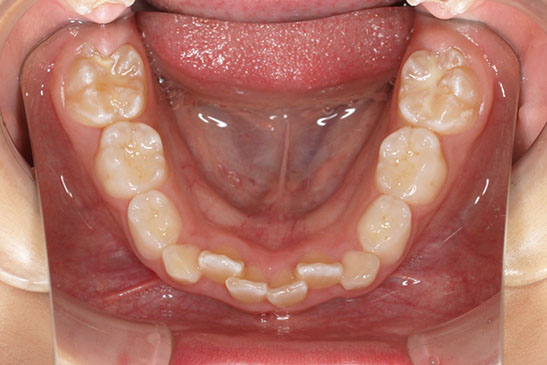

『前歯ががたついて生えてきた』 一般歯科から紹介の患者さんです。 上下4前歯に叢生がみられます。かみ合わせが深く、過蓋咬合。 上顎前歯は舌側傾斜。 永久歯の萌出スペースが上下とも5mmほど足りませんし、 おそらく、これから生えてくる犬歯は八重歯になる状況です。 治療方針としては、小児矯正で叢生(がたつき)を減らし、 永久歯列が生えてから、中学生ごろから本格矯正(マルチブラケット装置)を行います。 十分に側方拡大でスペースを確保し、更に、まだ生えていない永久歯の位置と方向が良ければ、きれいに生えそろうことにより、本格矯正での治療が必要ない場合もありますが頻度的には少ないです。 ある程度はきれいに生えてきても、左右の歯の高さの違いや、歯の回転、角度のズレが残る場合が多いからです。 その多少のがたつきが気にならないのでしたら、小児矯正で終了です。

小児矯正での早期治療で、側方拡大による十分なスペース確保をしていたことと、口唇の前突傾向がなかったことから、